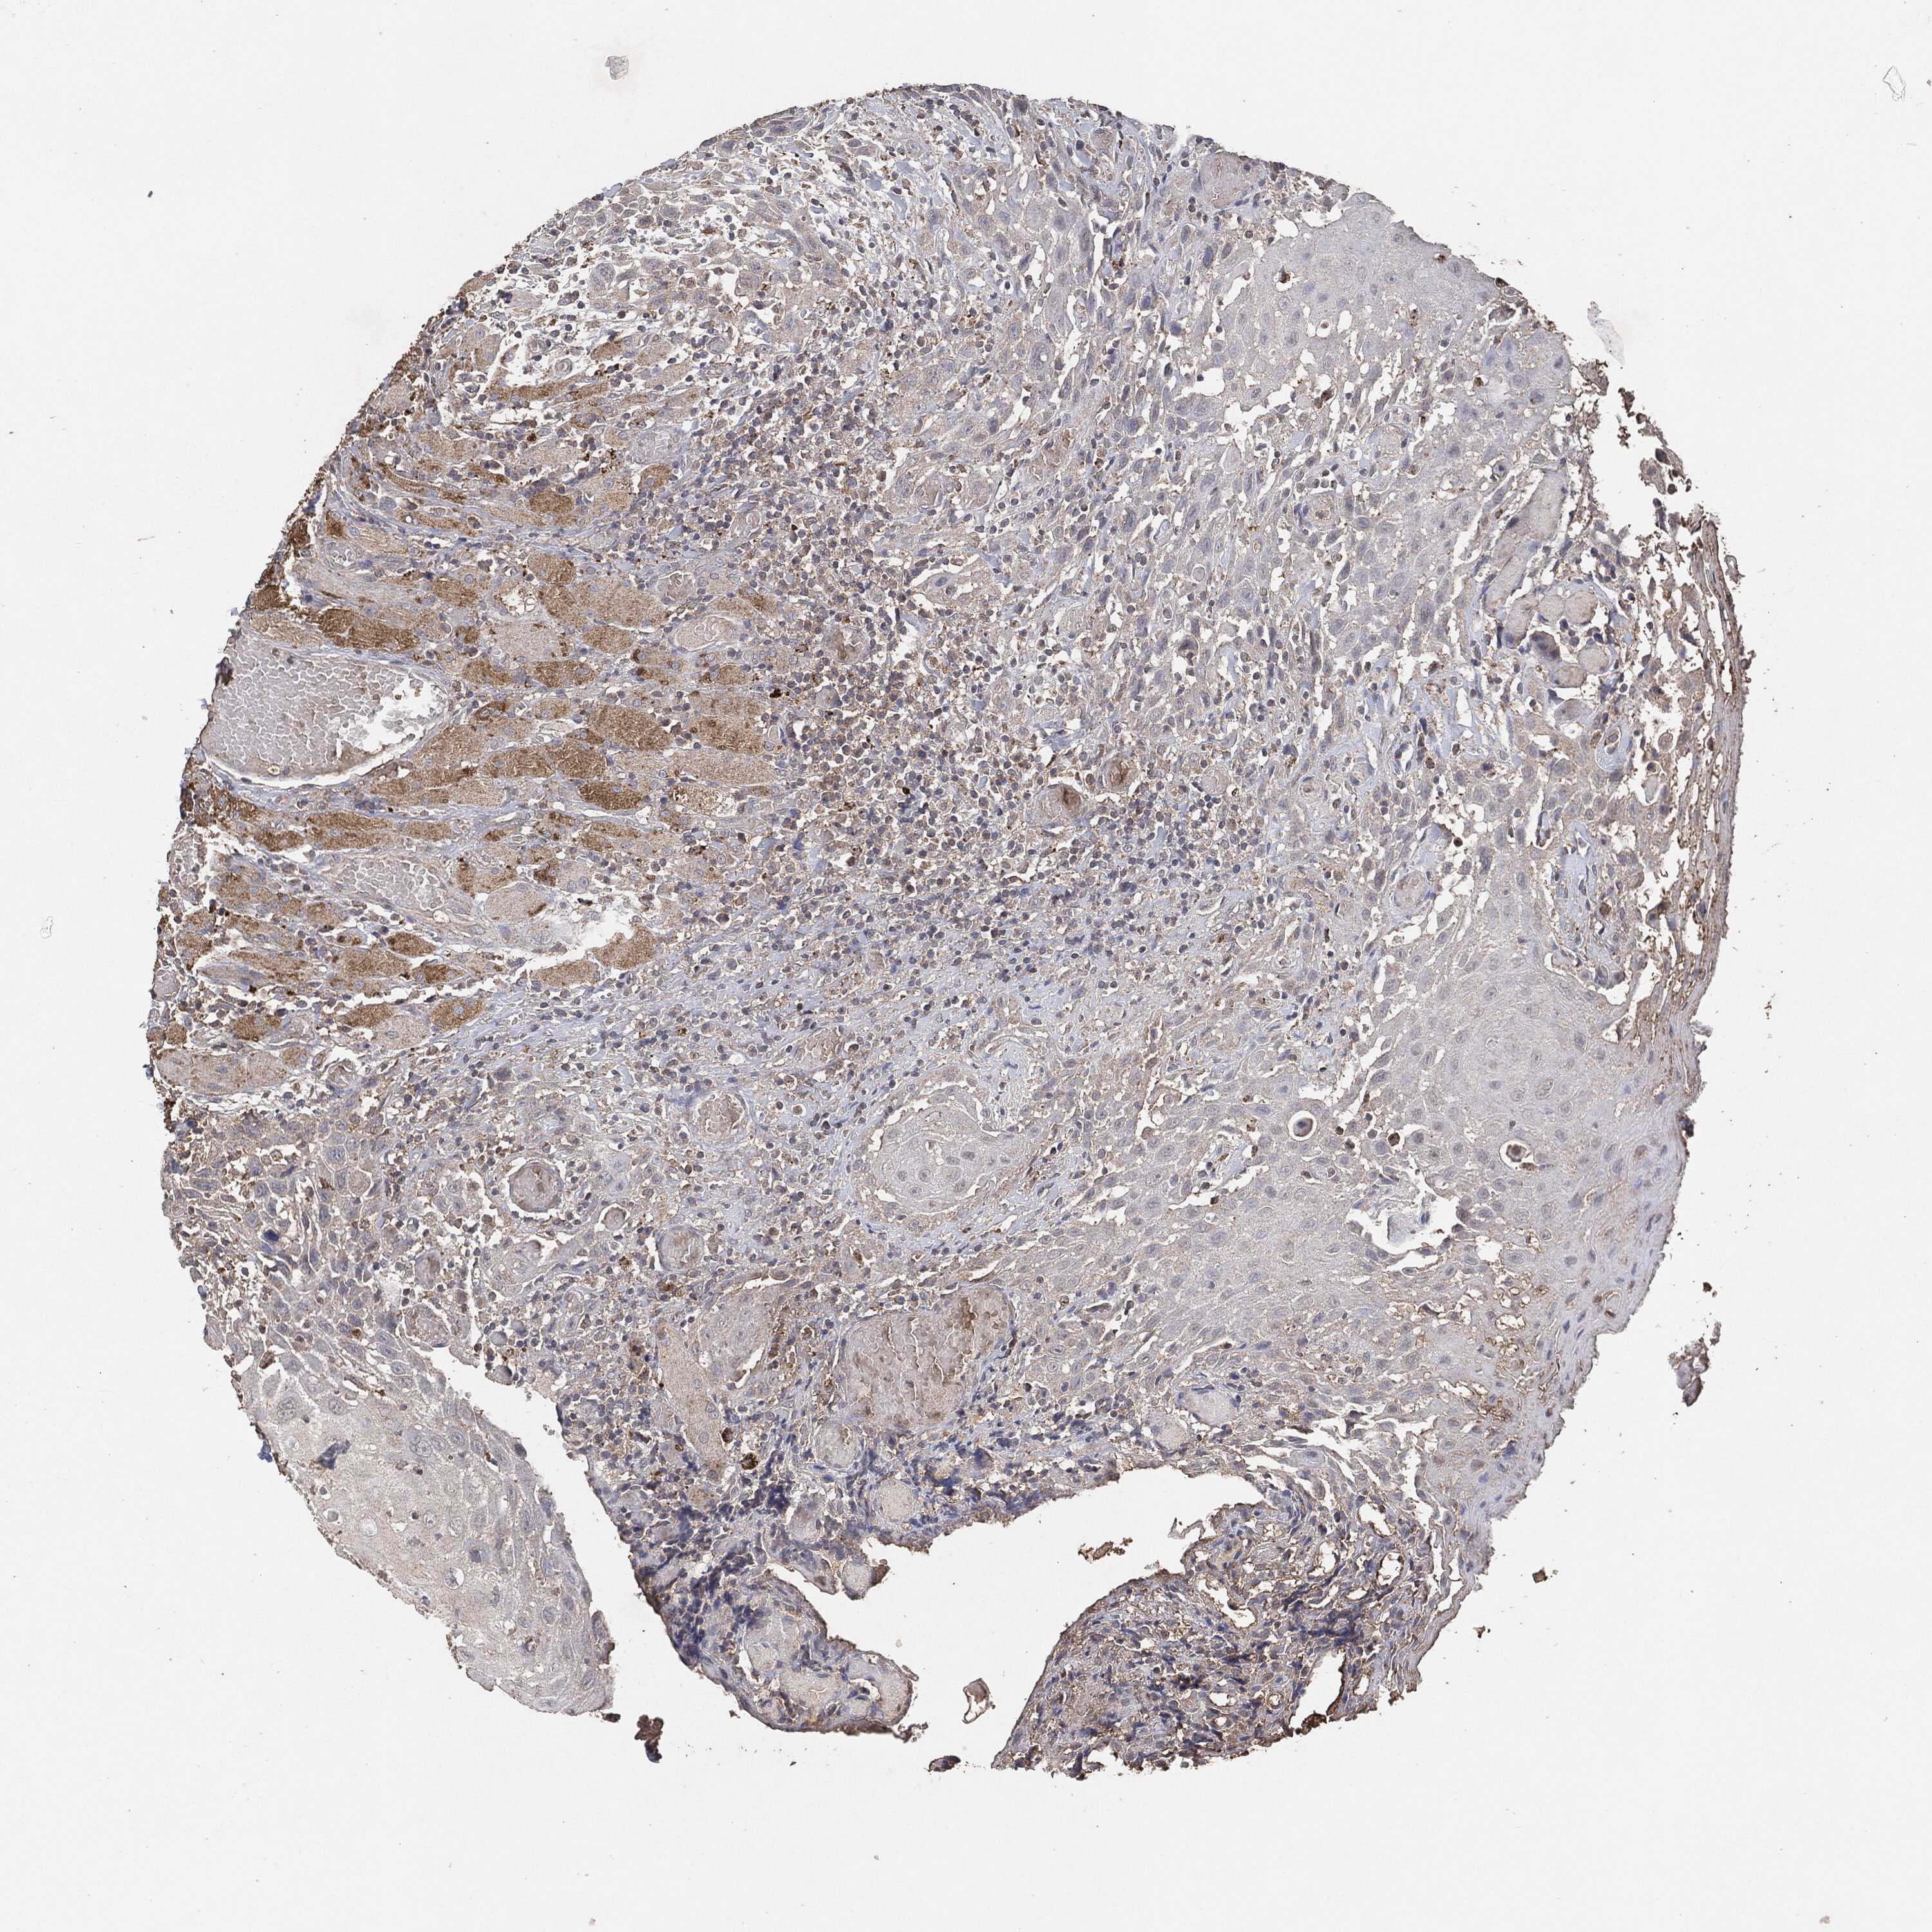

HEAD AND NECK CANCER - Protein expressioni

A mouse-over function shows sample information and annotation data. Click on an image to view it in a full screen mode. Samples can be filtered based on level of antibody staining by selecting one or several of the following categories: high, medium, low and not detected. The assay and annotation is described here.

Antibody stainingi

Antibody staining in the annotated cell types in the current human tissue is reported as not detected, low, medium, or high, based on conventional immunohistochemistry profiling in selected tissues. This score is based on the combination of the staining intensity and fraction of stained cells.

Each image is clickable and will lead to virtual microscopy that enables deeper exploration of all samples and also displays staining intensity scores, fraction scores and subcellular localization as well as patient and tissue information for each sample.